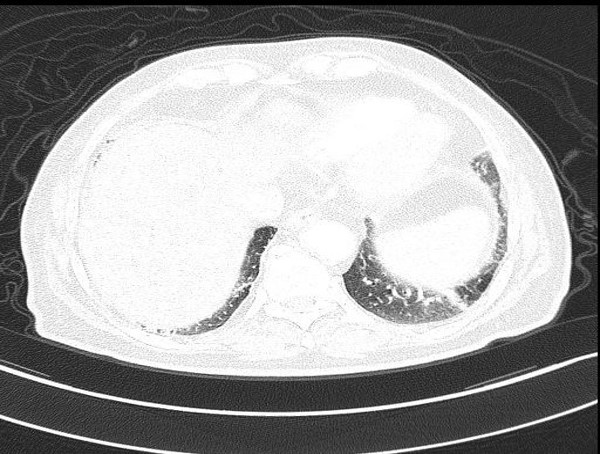

2018-05-19上腹部CT检查

腹部CT扫描示:肝左叶见肿块影,大小约4*3cm,肝左叶占位,考虑肝ca可能。

2018-05-19胸部CT检查:未见明显异常。

初步诊断:肝脏恶性肿瘤